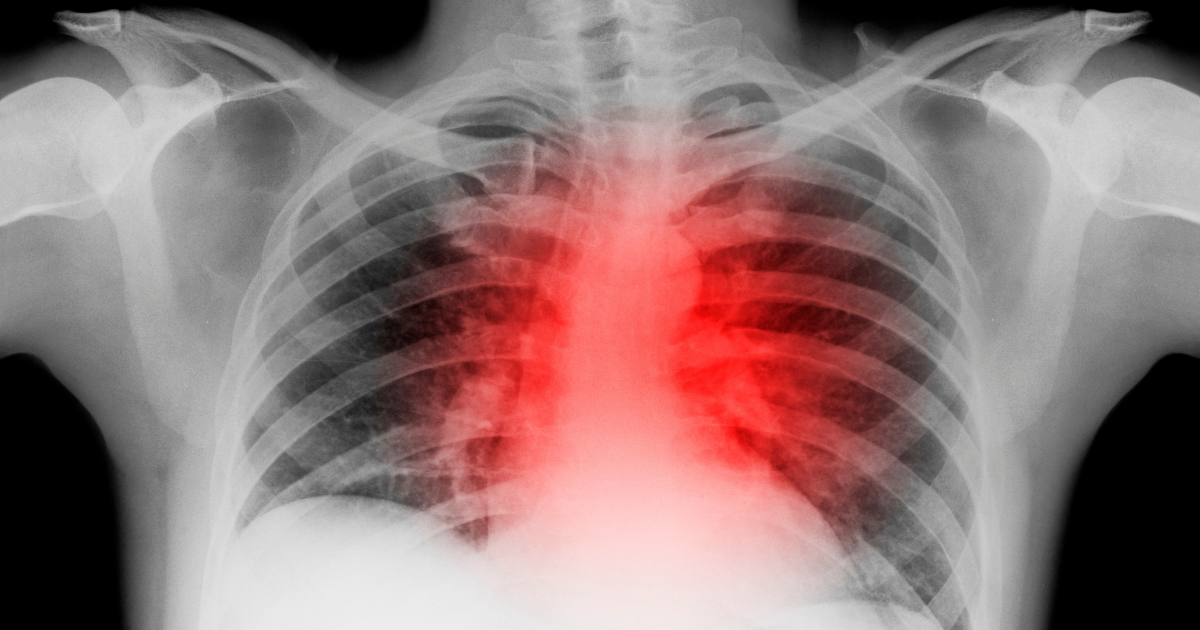

Verve Therapeutics, backed by Google Ventures, says Crispr gene editing to reduce humans' bad cholesterol, reducing heart attacks.